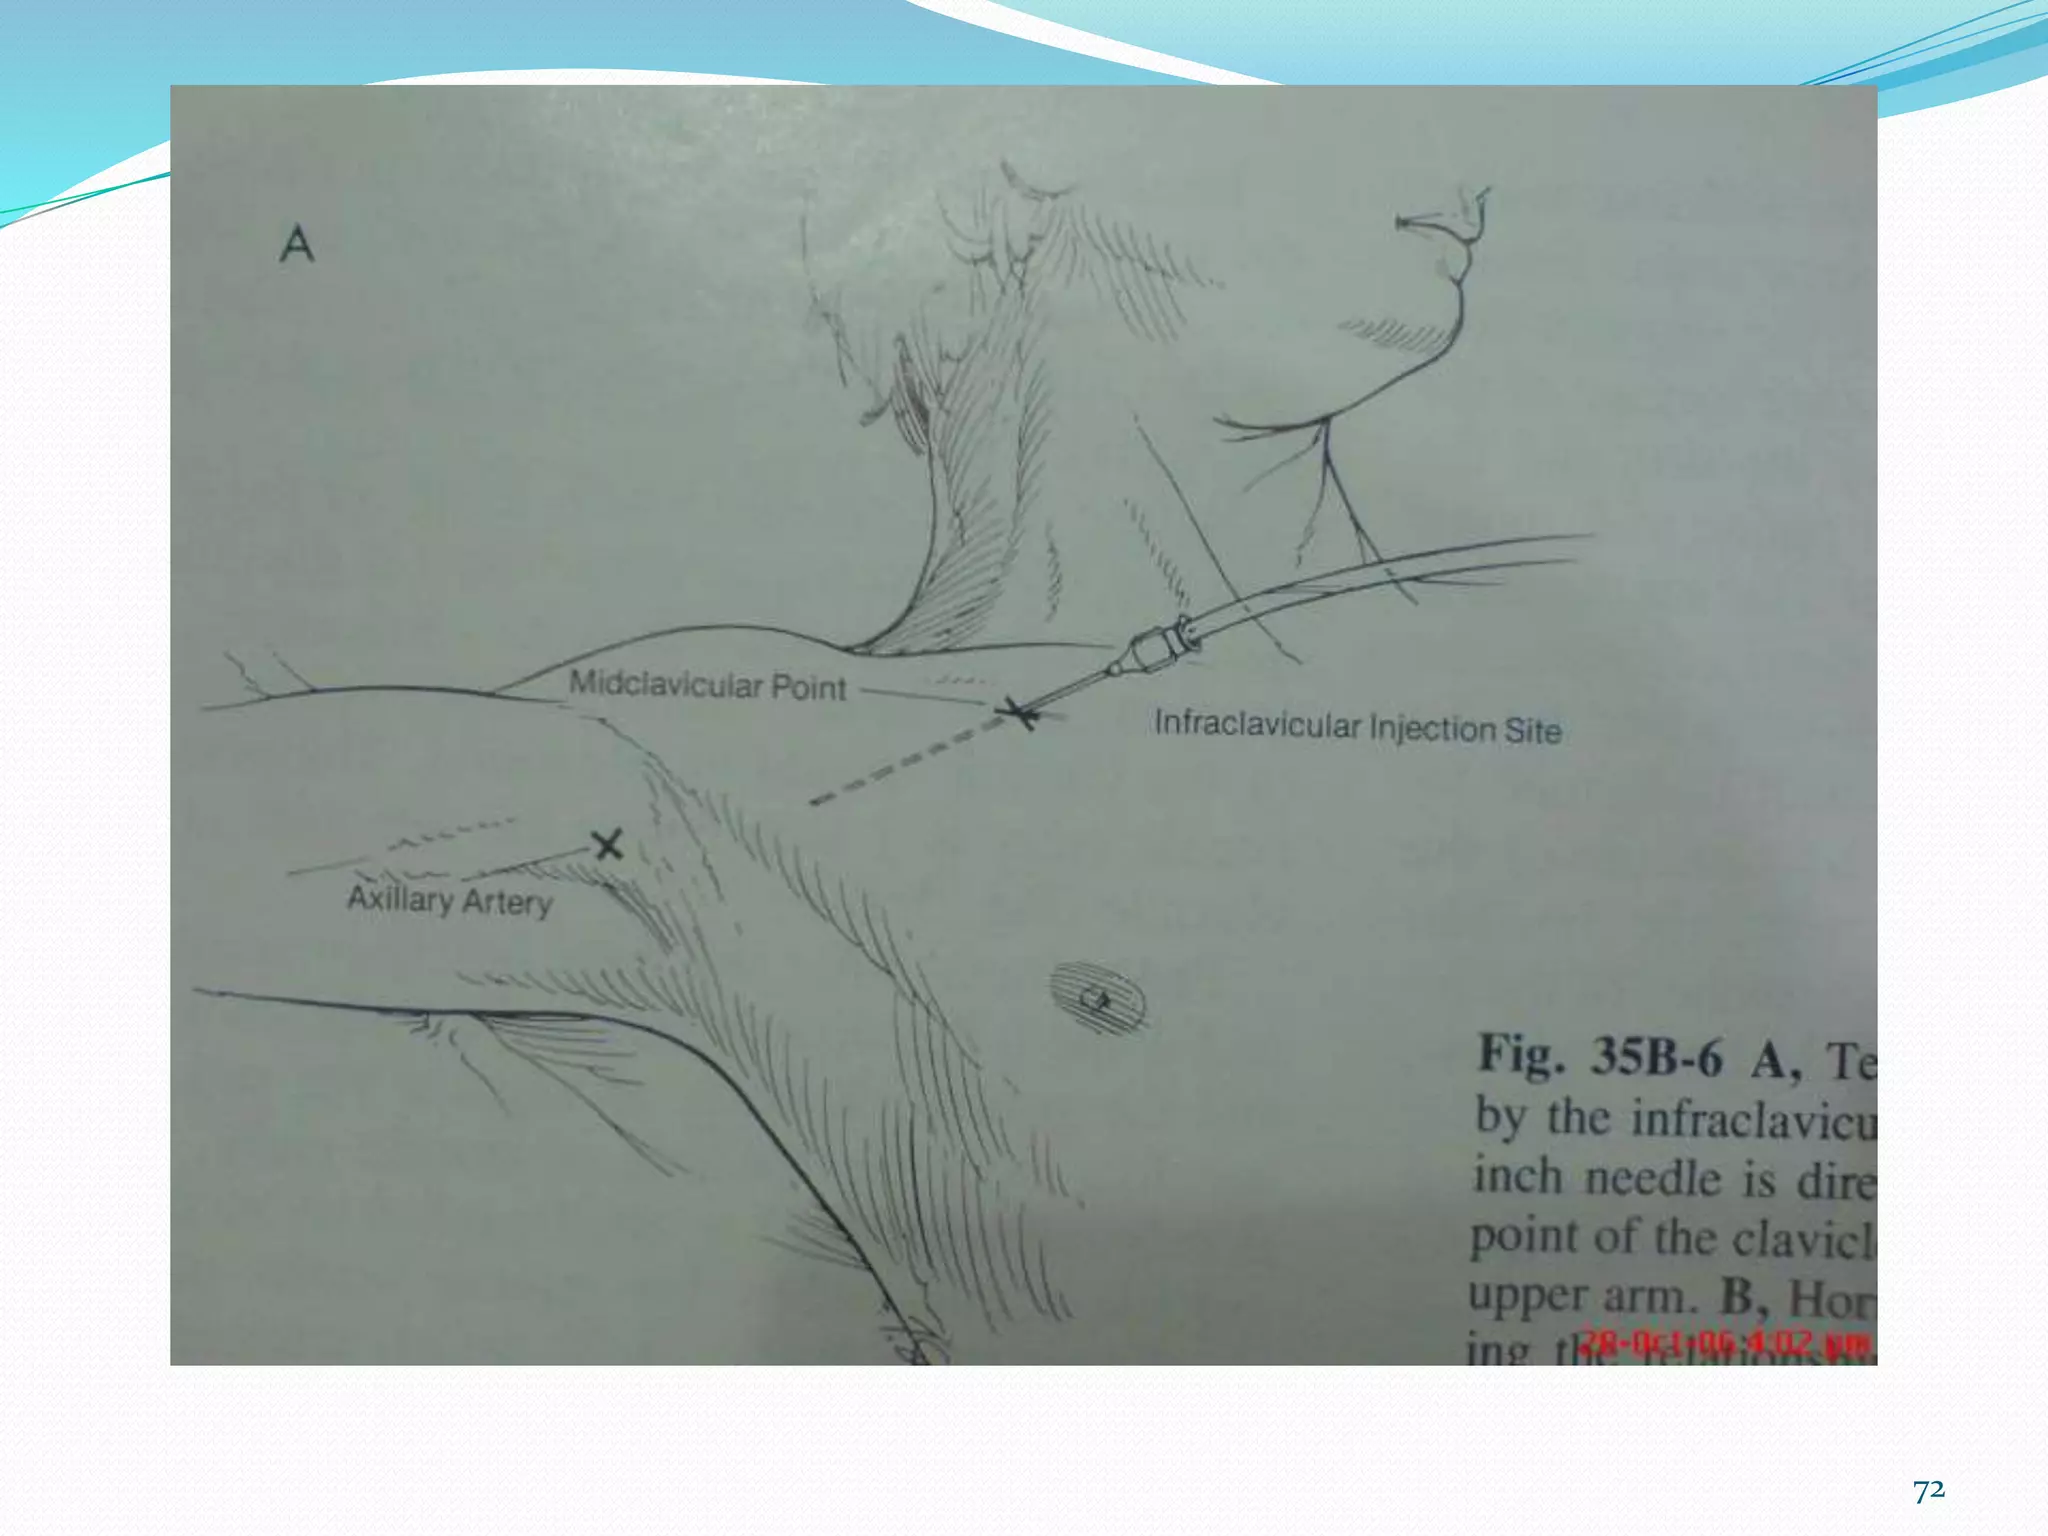

This document provides an overview of brachial plexus anatomy and techniques for brachial plexus nerve blocks. It begins with a description of the brachial plexus formation from cervical and thoracic nerve roots and its branching pattern. Four main approaches for brachial plexus nerve blocks are described: interscalene, supraclavicular, infraclavicular, and axillary. Details are provided on the anatomy and techniques for performing interscalene and supraclavicular brachial plexus blocks. Ultrasound guidance is discussed as an advancement which allows real-time visualization of needle and nerve. Complications are also summarized.